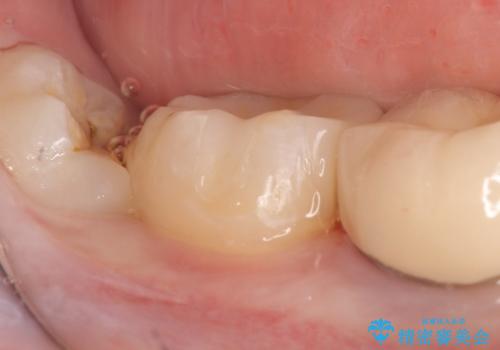

- 右下7の銀歯を白くしたいといらっしゃった方の症例です。

銀歯及び虫歯を除去後、セラミックインレーで修復を行いました。

当院のセラミックインレーはemaxという強度と審美性に優れた材料を使用しています。

またプレス方式でインレーを製作しているため、削り出しで製作するCADCAMより優れた適合性も持ち合わせており、虫歯が再発しにくい修復物です。